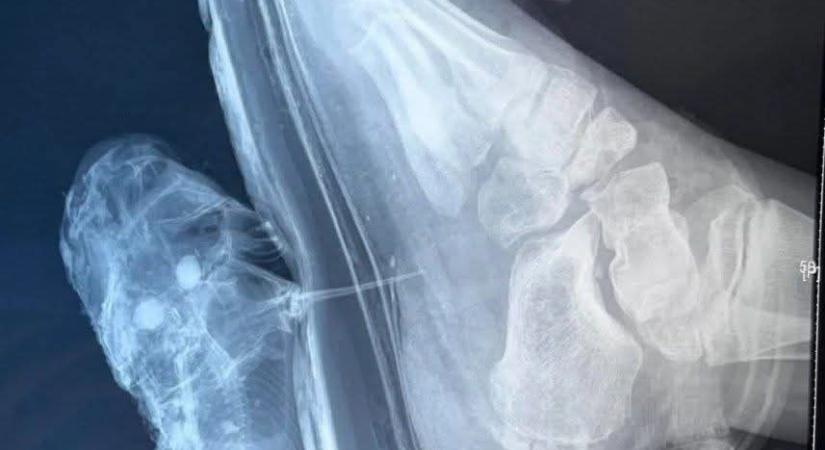

A magyar horgászok egyik legnagyobb ellensége nem egy óriáshal, hanem egy apró, invazív faj, amely első ránézésre ártalmatlannak tűnhet, a hal rendkívül fájdalmas sérüléseket tud okozni az óvatlan kezeknek.